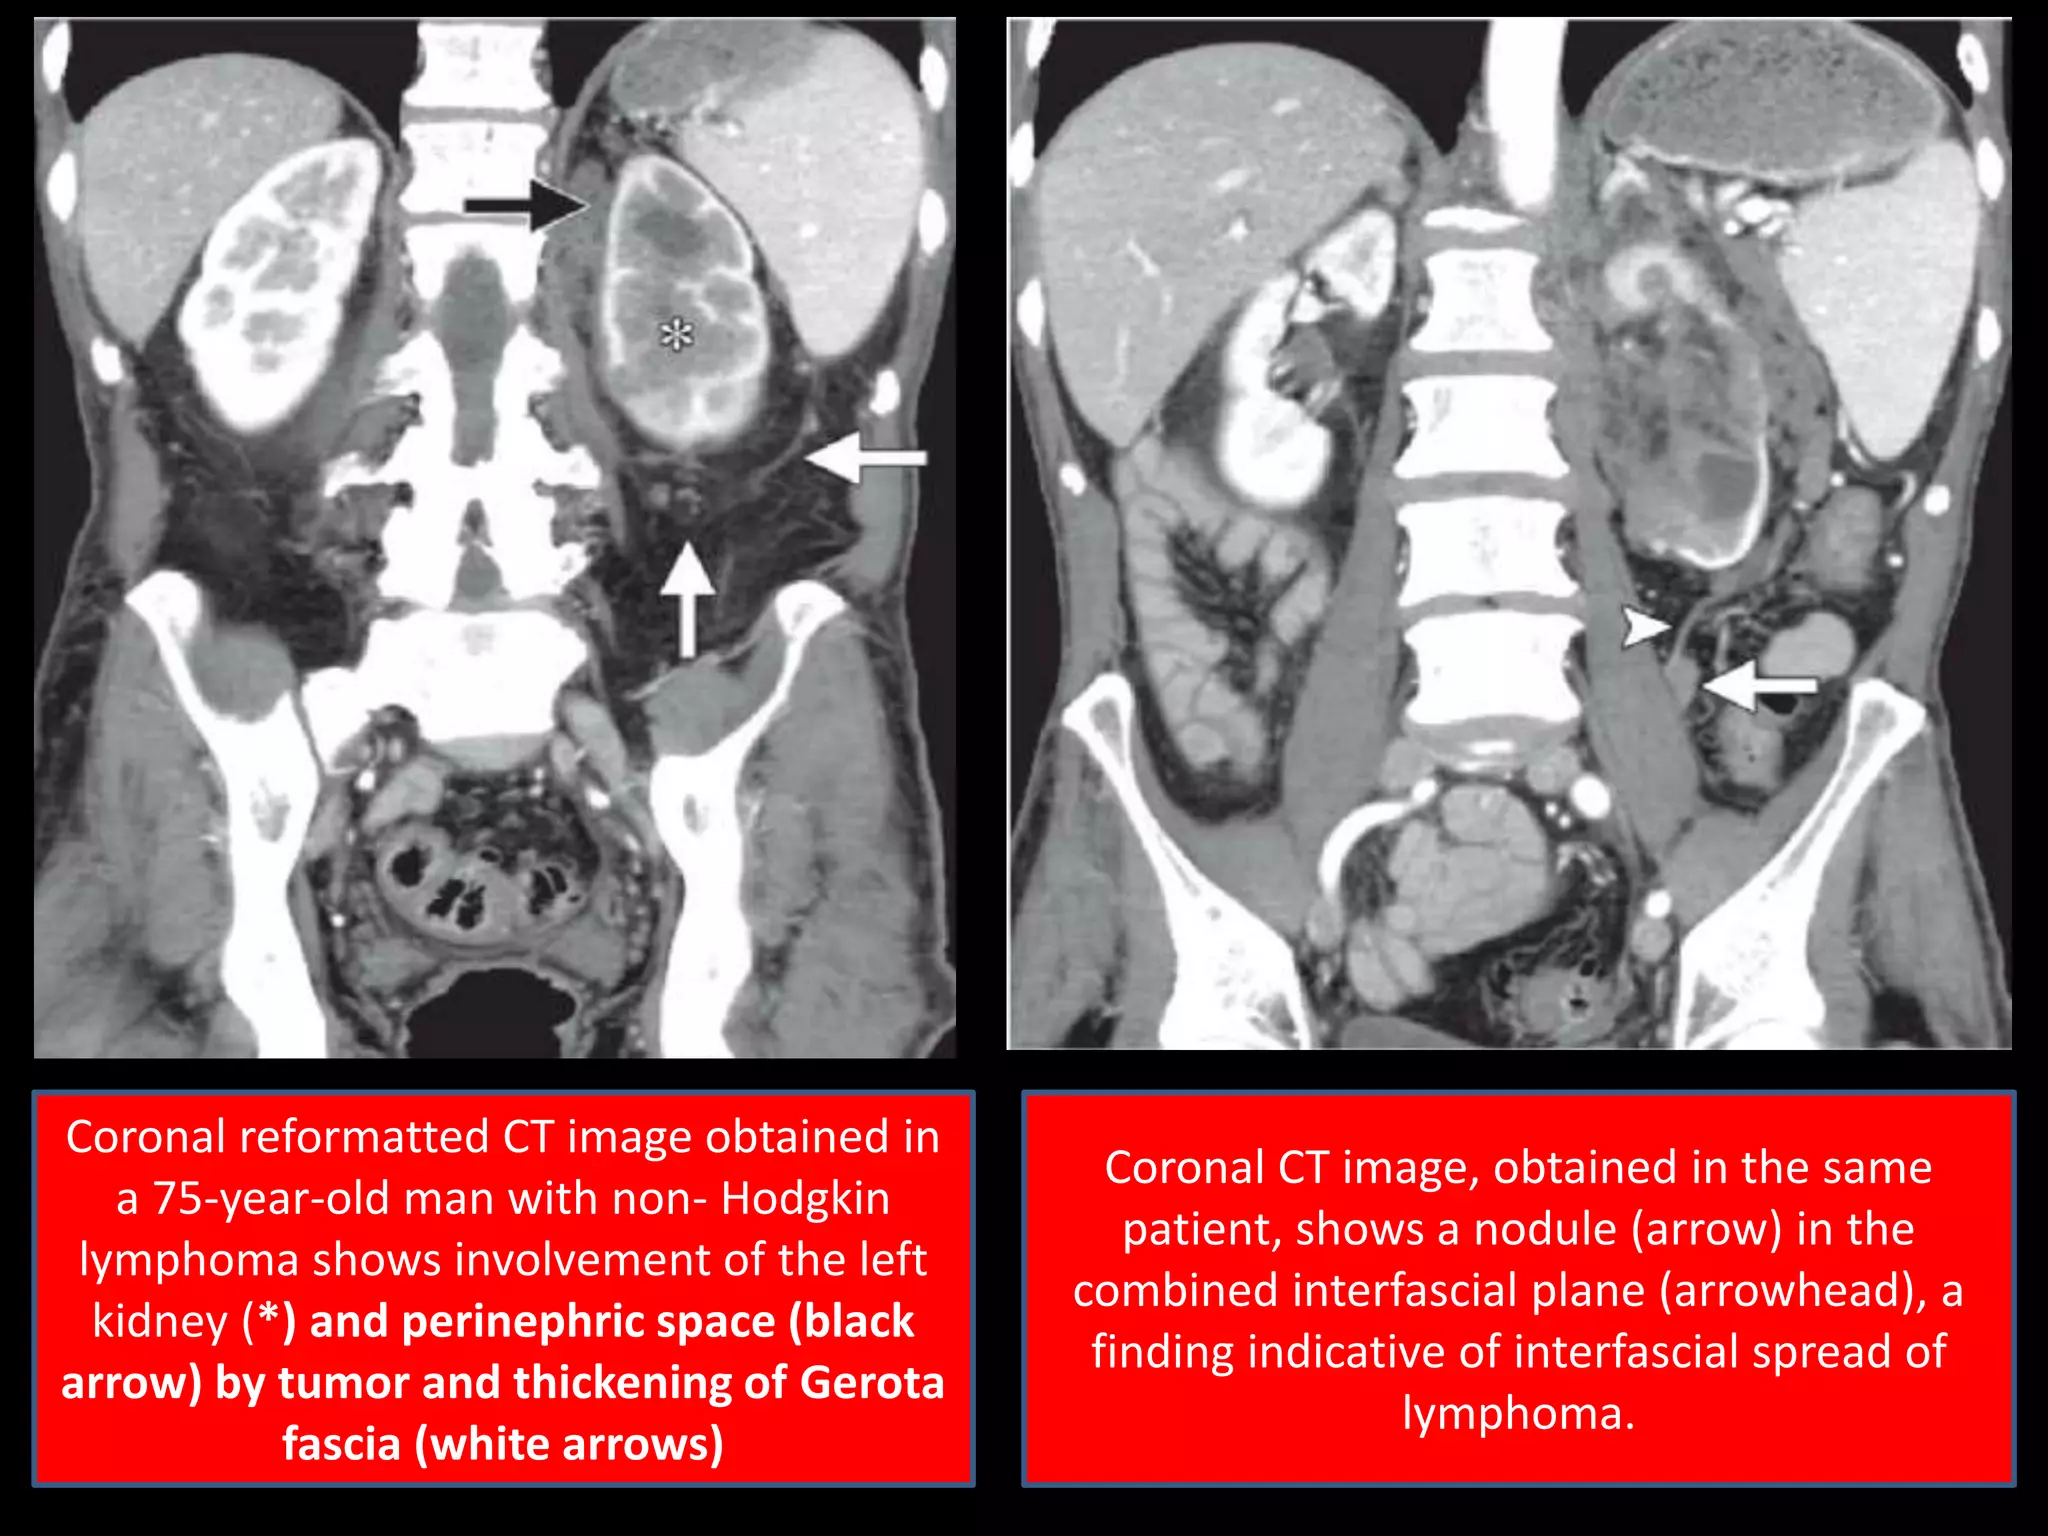

Coronal reformatted CT image obtained in

a 75-year-old man with non- Hodgkin

lymphoma shows involvement of the left

kidney (*) and perinephric space (black

arrow) by tumor and thickening of Gerota

fascia (white arrows)

Coronal CT image, obtained in the same

patient, shows a nodule (arrow) in the

combined interfascial plane (arrowhead), a

finding indicative of interfascial spread of

lymphoma.